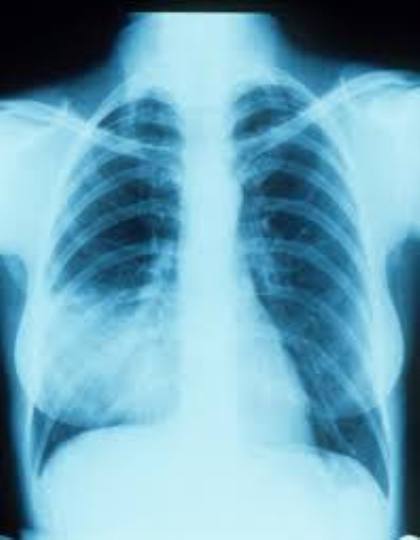

एड्स रोगियों में टीबी चिन्ता का विषय बनी हुई है. इस साल 700 रोगी जिले में एड्स बीमारी की भर्ती हुए हैं, इनमें 70 रोगियों में टीबी का संक्रमण मिला है. एड्स पीड़ितों में से 10 प्रतिशत रोगियों में टीबी की पुष्टि हो रही है और ये उनकी मौत की वजह बन रही है. एड्स और टीबी मिलकर मरीज पर घातक असर डाल रहे हैं.

गोरखपुर बीआरडी मेडिकल कॉलेज में अक्टूबर 2007 से लेकर अब तक 19,742 एड्स रोगियों का पंजीकरण हुआ है. इनमें जीवित रोगियों की संख्या 5,233 है, जिसमें गोरखपुर जिले के 4,504 रोगी और अन्य जिलों से 729 रोगी शामिल है. इन सबके बीच एड्स रोगियों के लिए टीबी की बीमारी जानलेवा साबित हो रही है.

एड्स रोगियों में टीबी संक्रमण को देखते हुए सरकार ने उनकी टीबी की जांच अनिवार्य कर दी है. विशेषज्ञों की मानें तो इस बीमारी का अभी तक कोई सटीक इलाज नहीं है इसलिए बचाव ही इसका इलाज है. इस रोग के प्रति जागरूक करने के लिए हर वर्ष एक दिसंबर को विश्व एड्स दिवस मनाया जाता है.